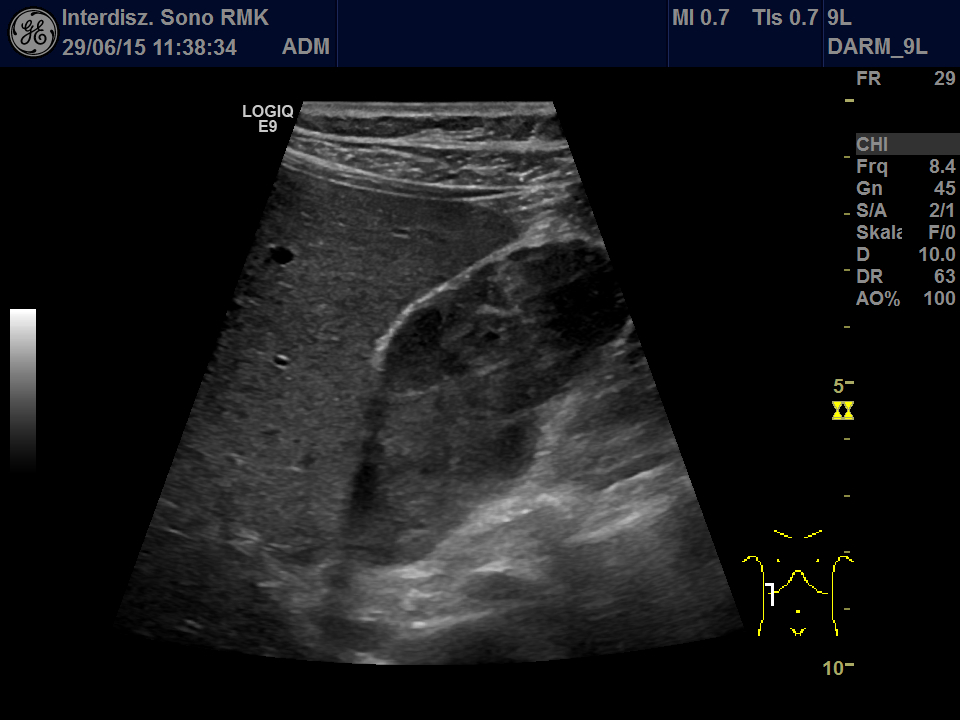

A 61 year old man was admitted to our hospital due to acute GI-bleeding. The man had been completely healthy until than and did not need any medications. One year ago a small melanoma on the head had been removed in toto. Routine ultrasonography before endoscopy showed echogenic material in the gallbladder (Fig. 1 + 2, Video 1). First gallbladder sludge was suspected. Because of its inhomogeneity in an additional linear array examination and a Doppler examination performed. Here arterial vessels in the gallbladder lumen were detected, thereby proving solid tissue (Video 2).

In addition, a contrast study (CEUS) was performed: This showed multiple polypoid tumors in the gallbladder lumen with strong contrast enhancement in the arterial phase and rapid washout (Fig. 3 + Video 3). Thus the echos in the gallbladder were no sludge but an intraluminal tumor! Only CEUS revealed the extend of tumor masses filling nearly the complete gallbladder.

Echogenic material in the gallbladder lumen mostly is caused by thickened bile: “sludge”. Clumped together sludge may imitate gallbladder polyps. Vice versa polypoid tumors can imitate sludge, especially in cases of hasty US examination. In any case of doubts you should use high-frequency linear probe, examination in left side position und color Doppler. Vessels in the lesion prove a neoplastic polyp witch may be benign or malign.

As shown in this case CEUS is even more sensitive in detecting tumor vascularization. CEUS in case of doubt is an excellent and reliable tool to distinguish between tumor tissue, sludge and concrements.

Figure 2: Second look using the linear array: Note the inhomogeneity of the echos in the lumen. Left side position does not cause any changes. Also note the well preserved wall of the gallbladder.

Video 2: Second look using the linear array and Doppler: Using low PRF several arterial branches inside the gallbladder can be detected. Note the inhomogeneity of the echos in the lumen.